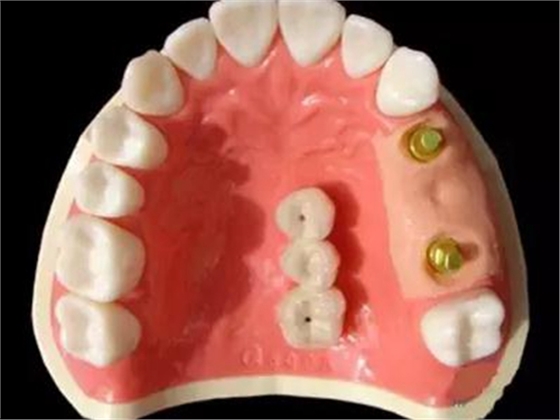

種植支持式固定義齒外展隙面積影響食物嵌塞

8月13日在線發(fā)表于《牙周病學(xué)雜志》(J Periodont)的一項(xiàng)橫斷面研究顯示,種植支持式固定義齒和鄰牙間的食物嵌塞更易發(fā)生于鄰接觸喪失及外展隙表面積(ESA)增加的情況下。食物嵌塞降低了患者的總體滿意度。外展隙尺寸影響牙周/種植體周黏膜的狀態(tài)及種植體的骨水平。

本研究納入了100例患者(55 例男性,45 例女性),平均年齡56歲(27~83歲),共150個(gè)固定義齒的215個(gè)外展隙。牙周/種植體周?chē)つ顟B(tài)、外展隙尺寸及患者總體滿意度作為解釋變量。

結(jié)果在種植支持式固定義齒和鄰牙間的215個(gè)外展隙中,96個(gè)(44.7%)有食物嵌塞。鄰接觸喪失外展隙較緊密接觸者更易發(fā)生食物嵌塞(P=0.009)。鄰面外展隙的食物嵌塞降低了總體滿意度(P=0.012)。在外展隙參數(shù)中,僅ESA明顯影響食物嵌塞(P=0.034)。不同的外展隙尺寸對(duì)牙周/種植體周黏膜狀態(tài)和種植體骨水平有顯著影響。